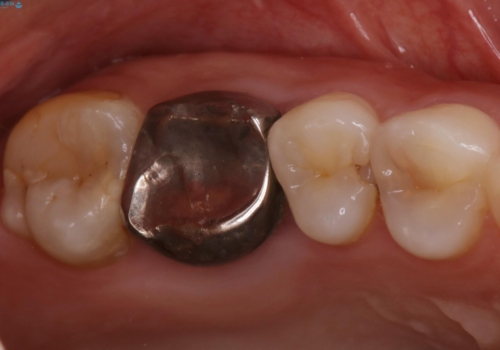

歯の間に食べ物がよく挟まるのを治したい

- 右上4、5間にフロスのひっかかりがあり、レントゲンから隣接面う蝕を確認しました。う蝕除去後は両歯にCADCAMインレーをセットしています。

歯の隣接面を正確に合わせることによって、物が詰まりにくく、再びう蝕になる確率を下げてくれます。